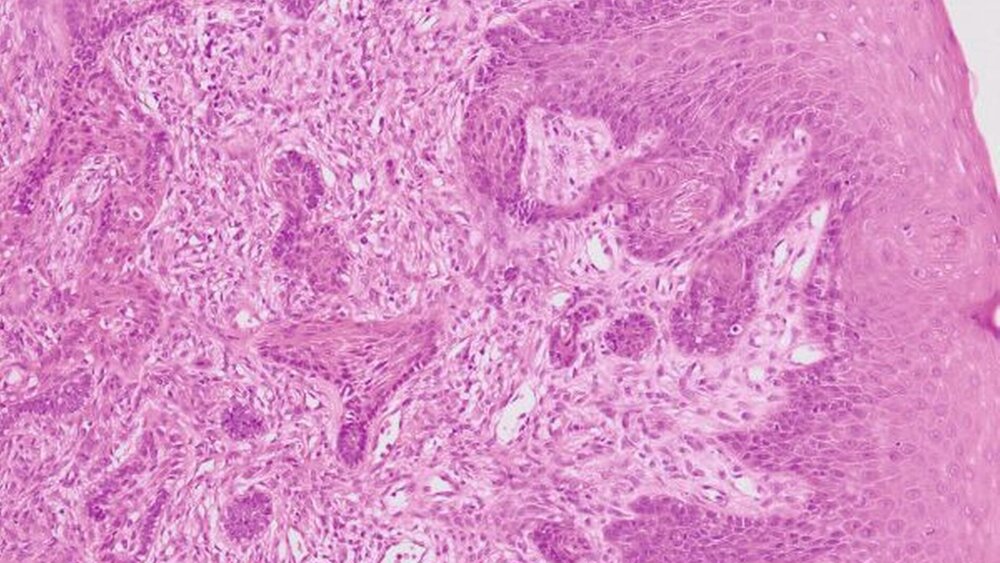

In der histopathologischen Aufbereitung zeigte sich ein teils trabekulär, teils solide wachsender Tumor mit Ausbildung polygonaler, unregelmäßig verzweigter konfluierender Zellnester, die mit breiter Invasionsfront an den basal gelegenen Knochen heranreichten und diesen oberflächlich erodierten, aber nicht infiltrierten (Abbildungen 3 und 4). Gegenüber der Schleimhaut entstand der Eindruck als fusionierten die neoplastischen Proliferate mit dem Oberflächenepithel der Gingiva beziehungsweise schienen von diesem auszugehen.

Aufgrund des klinischen Erscheinungsbildes wird das periphere Ameloblastom bis zur definitiven histologischen Untersuchung häufig als Epulis oder als peripheres odontogenes Fibrom fehlinterpretiert. Eine eindeutige Diagnose lässt sich nur durch die histologische Untersuchung stellen. Typisch sind ein follikuläres und ein plexiformes Wachstumsmuster mit konfluierenden Zellnestern odontogenen Gewebes mit meist palisadenförmiger Abgrenzung gegenüber dem Bindegewebe. In der mikroskopischen Ansicht erweckt der Tumor den Anschein, als ginge er vom Epithel aus. Eine Knochenarrosion kann auftreten, bei einer ossären Infiltration kann der Tumor nicht mehr als peripheres Ameloblastom gewertet werden.